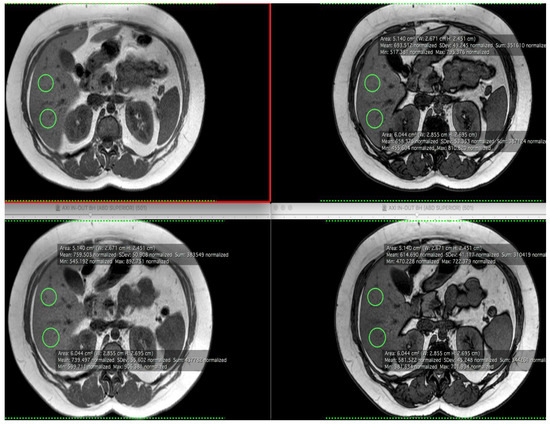

| % Liver Fat Fraction—Baseline | 17.14 (8.75) | 16.34 (13.52) | |

| % Liver Fat Fraction—12 weeks | 14.89 (11.87) | 16.43 (13.40) | 0.77 |

| p-value 2 | 0.10 | 0.96 | |

| Subcutaneous Fat Volume (cm2)—Baseline | 44.82 (13.54) | 46.56 (21.64) | |

| Subcutaneous Fat Volume (cm2)—12 weeks | 42.21 (7.98) | 49.11 (14.44) | 0.52 |

| p-value 2 | 0.28 | 0.95 | |

| Visceral Fat Volume (cm2)—Baseline | 14.20 (3.40) | 11.86 (1.32) | |

| Visceral Fat Volume (cm2)—12 weeks | 11.23 (4.32) | 11.94 (3.25) | 0.10 |

| p-value 2 | 0.02 | 0.83 | |

| Total Abdominal Area (cm3)—Baseline | 418.72 (114.41) | 416.81 (99.87) | |

| Total Abdominal Area (cm3)—12 weeks | 390.05 (82.32) | 418.82 (104.11) | 0.56 |

| p-value 2 | 0.13 | 0.91 |